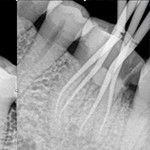

效果展示

根管治療 根管治療 根管治療 根管治療